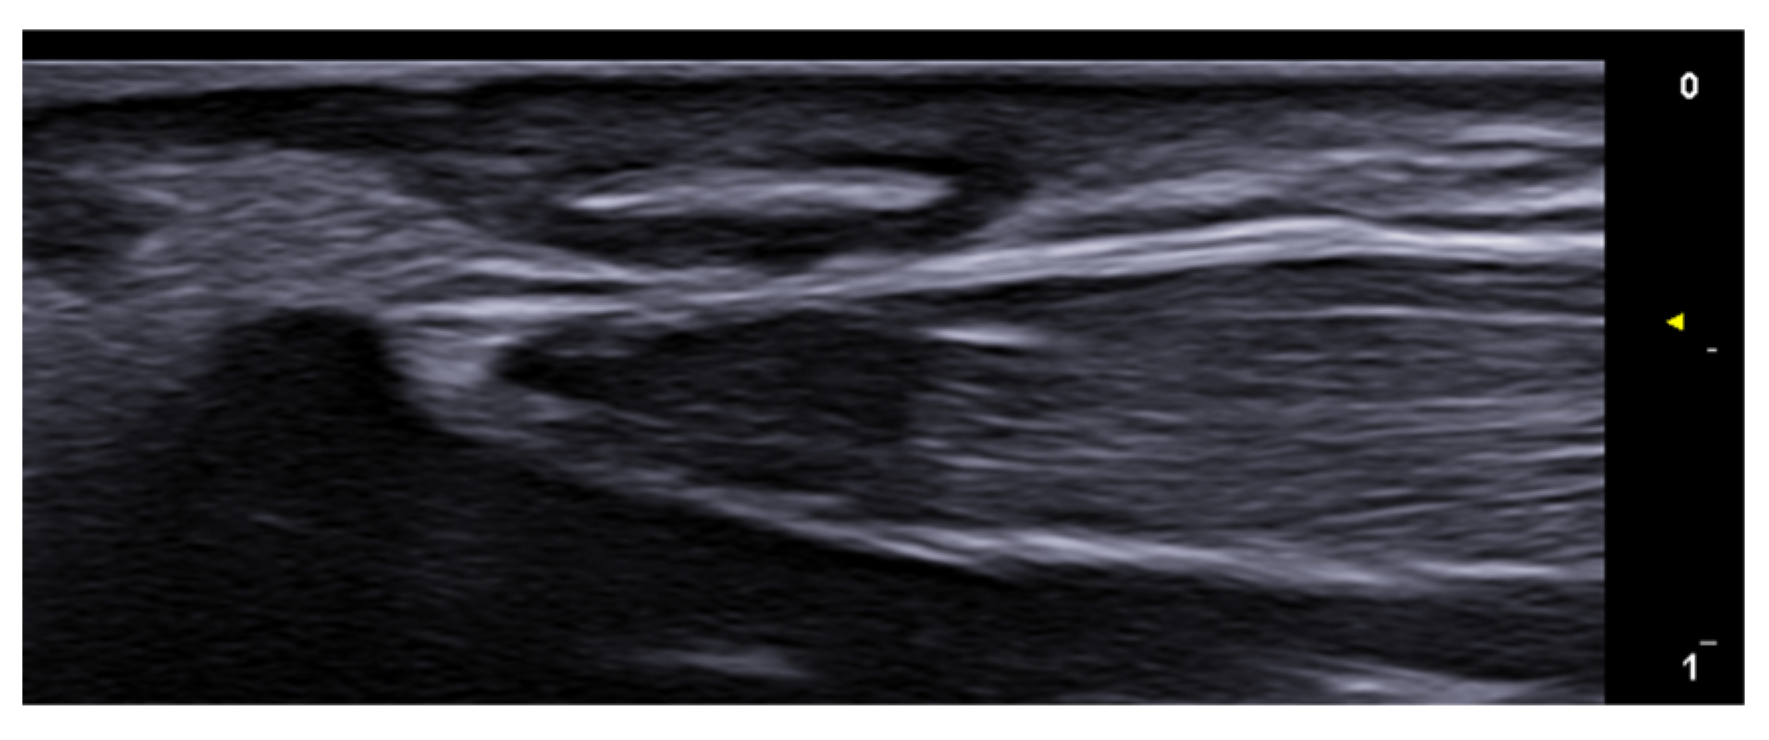

- Di Battista, M.; Vitali, S.; Barsotti, S.; Granieri, G.; Aringhieri, G.; Morganti, R.; Dini, V.; Della Rossa, A.; Romanelli, M.; Neri, E.; et al. Ultra-high frequency ultrasound for digital arteries: Improving the characterization of vasculopathy in systemic sclerosis. Semin. Arthritis Rheum. 2022, 57, 152105. [Google Scholar] [CrossRef] [PubMed]